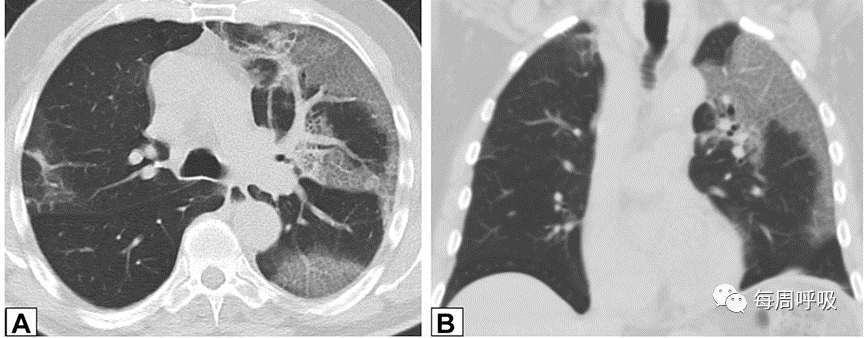

图9 微小结节。同一患者的高分辨率CT轴位扫描切面(A)和最大密度投影图像(B)。CT扫描图像显示双肺多发小实性结节,提示可能的恶性肿瘤或感染。CT扫描引导下的针吸活检结果与机化性肺炎的诊断一致。

图10 肿块42岁的患者,病态肥胖,有呼吸困难,右肺上叶(A)和右肺下叶(B)的轴位CT平扫图像显示双侧,胸膜下或周围肿块样实变区域。这些发现是非特异性的;活检结果提示机化性肺炎,类固醇治疗后消退。